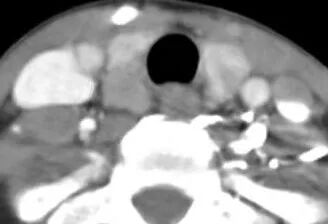

成都东篱医院 首例继发性甲旁亢手术 近期成都东篱医院在多学科协作(MDT)模式下,集结多学科技术力量(外一科、肾内科、超声科、麻醉科、病理科、检验科、放射科等),为一例继发性甲状旁腺功能亢进患者,成功实施我院首例“甲状旁腺全切除术+甲状旁腺自体移术”。 据悉,52岁的黄女士是一位尿毒症合并继发性甲状旁腺功能亢进患者。黄女士进行血液透析治疗已经11年,早在3年前就出现全身多关节疼痛、皮肤瘙痒,且血甲状旁腺激素(PTH)也在逐渐升高;虽长期服用药物治疗,但治疗效果有限。忍受病痛折磨的黄女士四处寻医,辗转来到成都东篱医院外一科,化验显示甲状旁腺素高达2693pg/ml,彩超检查发现甲状旁腺增生明显。 术前超声和CT增生甲状旁腺的表现 临床上对于继发性甲状旁腺功能亢进的治疗主要有药物治疗和手术治疗。外一科黄启荣主任介绍到:“当甲状旁腺进入结节性增生阶段后,常规的内科治疗大多无效,******的办法就是手术治疗。但甲状旁腺位于颈内深部,临近喉上神经、喉返神经、气管及食道等重要脏器,易损伤致严重并发症;加之尿毒症继发性甲旁亢患者身体情况较差,对手术及麻醉的耐受性差,围手术期管理非常困难,因而尽管目前急需手术治疗的继发性甲旁亢的尿毒症病人很多,但是因为手术风险高,难度大,开展该技术的医院较少。” 黄启荣主任组织全科认真研究分析了黄女士的病情,认为虽然困难重重,但手术是惟一的希望,决心利用“多学科联合诊疗”来寻求突破。外一科、肾内科、超声科、麻醉科、病理科、检验科、放射科等多个科室参与会诊、协调合作,共赴“战场”。 10月20日,为黄女士成功实施了“甲状旁腺全切除+左前臂甲状旁腺自体移植术”,手术过程非常顺利,甲状旁腺完整切除。术后甲状旁腺激素迅速恢复至正常水平(术前高达2693pg/ml,术后30分钟降至356pg/ml,术后第二天56pg/ml),未出现声音嘶哑、呛咳、喉头水肿等并发症,由甲旁亢引起的骨痛和瘙痒也明显缓解。因患者恢复良好,术后5天便顺利出院。 术中切除的4个甲状旁腺 待移植的甲状旁腺 该手术是我院成功开展的首例继发性甲旁亢手术,填补了我院在该治疗领域的空白,标志着我院在继发性甲状旁腺功能亢进治疗上取得了全新的突破!今后,我院继发性甲状旁腺功能亢进治疗将向MDT常态化开展,每位患者经MDT团队综合评估后量身定制手术方案,形成术前、术中、术后严密监测、精细化管理,将进一步提高中晚期继发性甲状旁腺功能亢进病人存活率及生活质量。